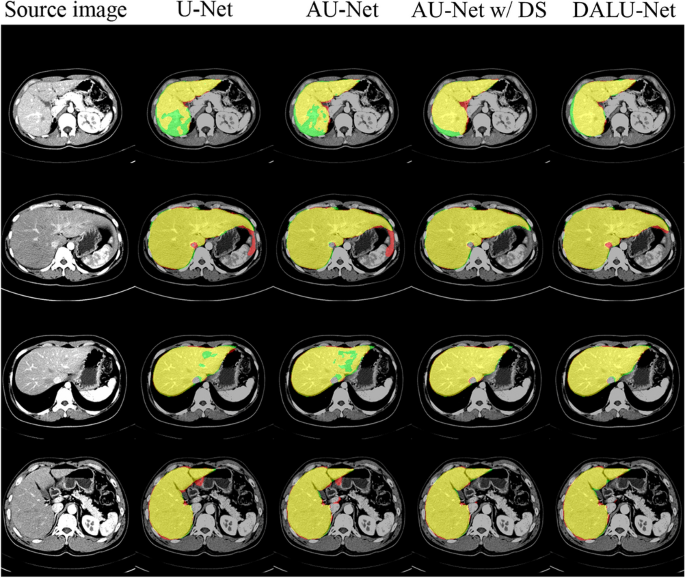

We analyzed the accuracy of the liver segmentation network. To this end, we compared the 3D U-Net, Attention U-Net, Attention U-Net with DS, and DALU-Net. Table 3 shows the performance of our method in the four validation datasets: (a) left lobe, (b) right lobe, (c) caudate lobe, (d) whole liver. We used evaluation metrics to measure the accuracy of the segmentation results: the higher the value of the evaluation metrics, the better the segmentation results. On the other hand, the smaller the Hausdorff distance was, the better were the results. Our method performed better than 3D U-Net in terms of segmentation accuracy (DSC), with 7% and 10% improvement in the whole liver and caudate lobe datasets, respectively. Figure 5 shows the visual assessment of the automated liver segmentation.

Examples of liver segmentation results at the axial view images for the various models. Segmentation results are color-coded: green is ground truth, red is automated segmentation, and yellow is the overlap between the ground truth and automated segmentation.

In this study, we showed that our proposed DALU-Net model, based on AG, DS, and CLSTM, can be trained to perform automated and accurate liver segmentation using abdominal CT data. We achieved high performance with a segmentation accuracy DSC of 0.899 for the whole liver. Compared to the reference model, 3D U-Net, the performance of the proposed model was improved by 7%. Table 3 presents the results of the AG, DS, and CLSTM models to the basic 3D U-Net model; whole liver segmentation accuracy improved by 3%, 3%, and 1%, respectively. Figure 5 presents the training results of the model. For the proposed DALU-Net model, segmentation results were more accurate than those of other models. We demonstrated that the segmentation accuracy increased with addition of each method.